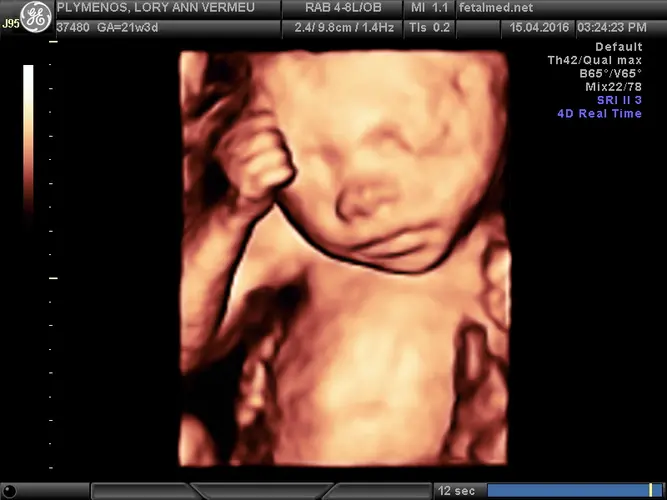

Seu bebê está passando por transformações impressionantes nesta semana! Com aproximadamente 600 gramas e 29 centímetros de comprimento, ele agora tem o tamanho de uma espiga de milho madura. O crescimento está acelerado, com um ganho médio de 170 gramas por semana, resultado principalmente do desenvolvimento muscular, ósseo e do início do acúmulo de gordura subcutânea que dará aquele aspecto mais rechonchudo característico dos recém-nascidos.

O rostinho do seu pequeno está quase completamente formado e cada vez mais adorável. Os cílios estão se desenvolvendo, as sobrancelhas ficam mais definidas a cada dia, e o cabelo começa a nascer na cabecinha. Uma curiosidade interessante: por enquanto, todos os fios capilares são completamente brancos, pois a pigmentação ainda não se desenvolveu. A cor definitiva do cabelo só aparecerá mais tarde na gestação ou até mesmo após o nascimento.

As ondas cerebrais fetais estão ativando os sistemas auditivo e visual, preparando seu bebê para perceber melhor o mundo ao redor. Ele já consegue reagir a sons externos e pode até mesmo responder ao toque na barriga da mamãe. Os movimentos estão mais coordenados e você provavelmente já consegue distinguir padrões nos períodos de atividade e descanso do bebê.